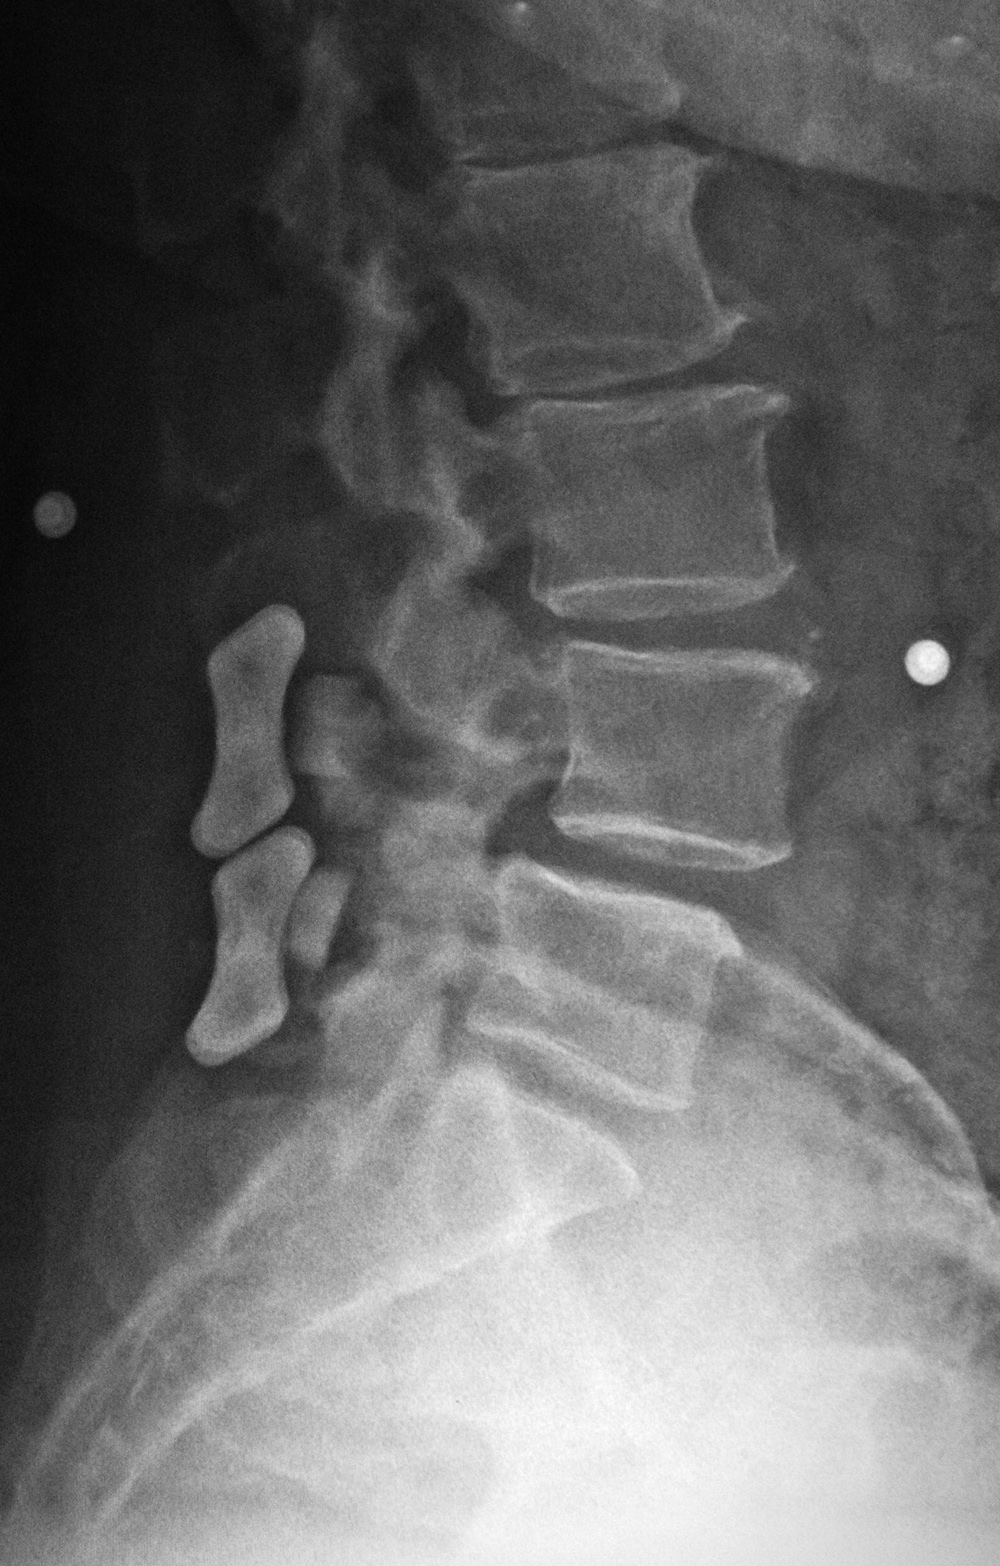

Harms vertebral cage (lateral view) |

Lumbar spine bony disk strut, pedicle screws, and pedicle rods (lateral view) |